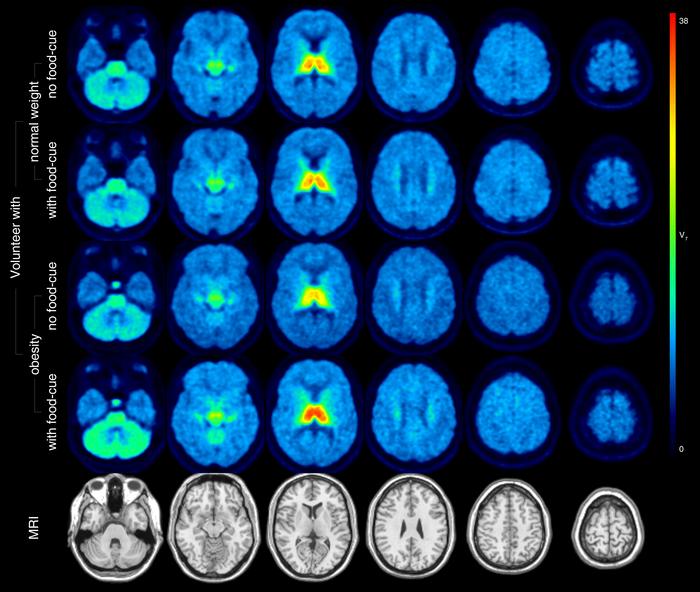

In the study, 15 individuals with obesity and 16 normal-weight controls underwent PET/MRI with 18F-flubatine twice on separate days, once while in a resting state and once while viewing food pictures. Total distribution volume of 18F-flubatine was estimated, and a visual analog scale was used to assess states of hunger/satiety, appetite, disinhibition, craving and taste. Eating behavior was also measured using the Three-Factor Eating Questionnaire (TFEQ).

In the resting state, no significant difference in total distribution volume of 18F-flubatine was noted between the participants with obesity and normal-weight controls. While viewing photos of food, however, the total distribution volume of 18F-flubatine was higher in the obese compared with normal-weight controls in the thalamus of the brain, particularly in those with a higher TFEQ score.